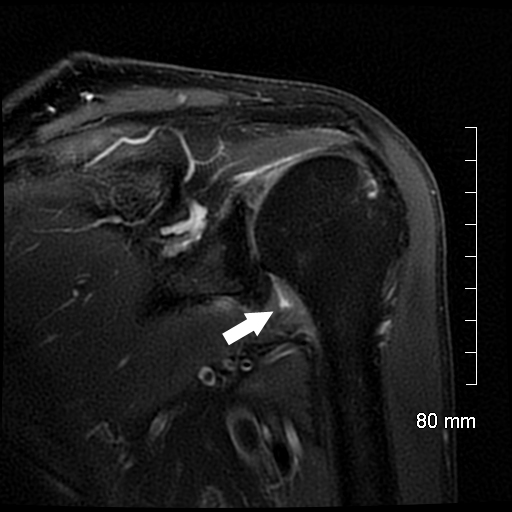

From www.indianradiology.com

Adhesive capsulitisMRI Sumer's Radiology Blog Adhesive Capsulitis Toe This overburdening leads to tissue damage and resultant discomfort. Capsulitis of the foot is caused by increased stress on the metatarsophalangeal joint at the base of the toe, which causes inflammation and. Adhesive capsulitis is a chronic fibrosing condition characterised by insidious and progressive severe restriction of both active. The root cause of capsulitis, a condition marked by joint pain,. Adhesive Capsulitis Toe.